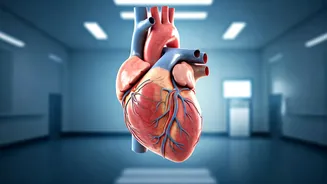

Bedtime and Heart Health

Recent studies point towards a connection between delaying bedtime regularly and an increased risk of heart problems. This indicates that people who persistently postpone their sleep schedule may be exposing themselves to adverse health consequences. The exact reasons for this link are still being explored, but research suggests that disrupted sleep patterns can influence various physiological processes. These processes include those affecting heart function. Prolonged sleep disruption may have effects on cardiovascular health by affecting blood pressure, heart rate variability, and inflammatory responses. Prioritizing consistent and timely sleep schedules is thought to be an essential step for overall health. Ensuring adequate sleep can promote a healthier lifestyle and may support long-term cardiovascular well-being. This research highlights the importance of taking care of yourself for a healthier future.